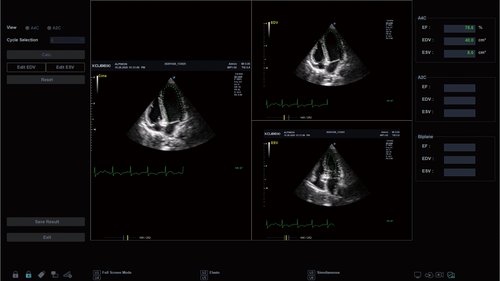

• MP1-5X (1-5 MHz) für Ultraschalluntersuchungen in Bereichen Kardiologie, Abdomen, Pädiatrie, EM, TCD

• SP3-8T (3-8 MHz) für Ultraschalluntersuchungen in Bereichen Kardiologie, Abdomen, Pädiatrie, EM

• 23,5 Zoll Full HD LED Monitor

• Automatisierte Messungen und Workflow (optional)